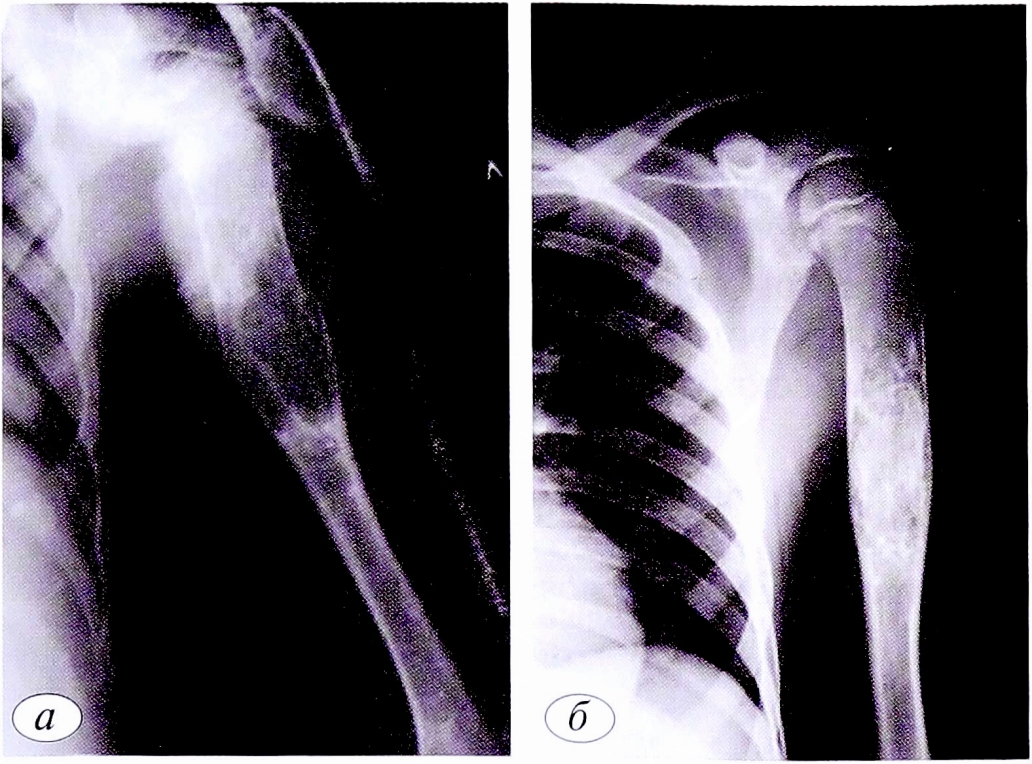

Рентгенологическое исследование позволяет выявить локализацию и характер перелома. Рентгенологическое обследование начинали после клинического осмотра и уточнения области исследования. Объем обследования определяли исходя из жалоб, клинической картины и допустимых доз облучения (для детей) (рис. 1).

Рис. 1. Пациент К.,9 лет. Диагноз: патологический перелом левой плечевой кости на фоне кисты кости. Рентгенограммы левой плечевой кости в гипсовой повязке (а), через 6 нед после снятия гипсовой повязки (б): отмечаются консолидация перелома и признаки репарации кисты кости.

Fig. 1. Patient К.,9 years old. Diagnosis: Pathological fracture of the left humerus due to bone cysts. a — radiograph of the left humerus in a plaster cast; б — radiograph of the left humerus 6 weeks after removal of the plaster cast. X-ray consolidation of the fracture, and signs of repair of the bone cyst.